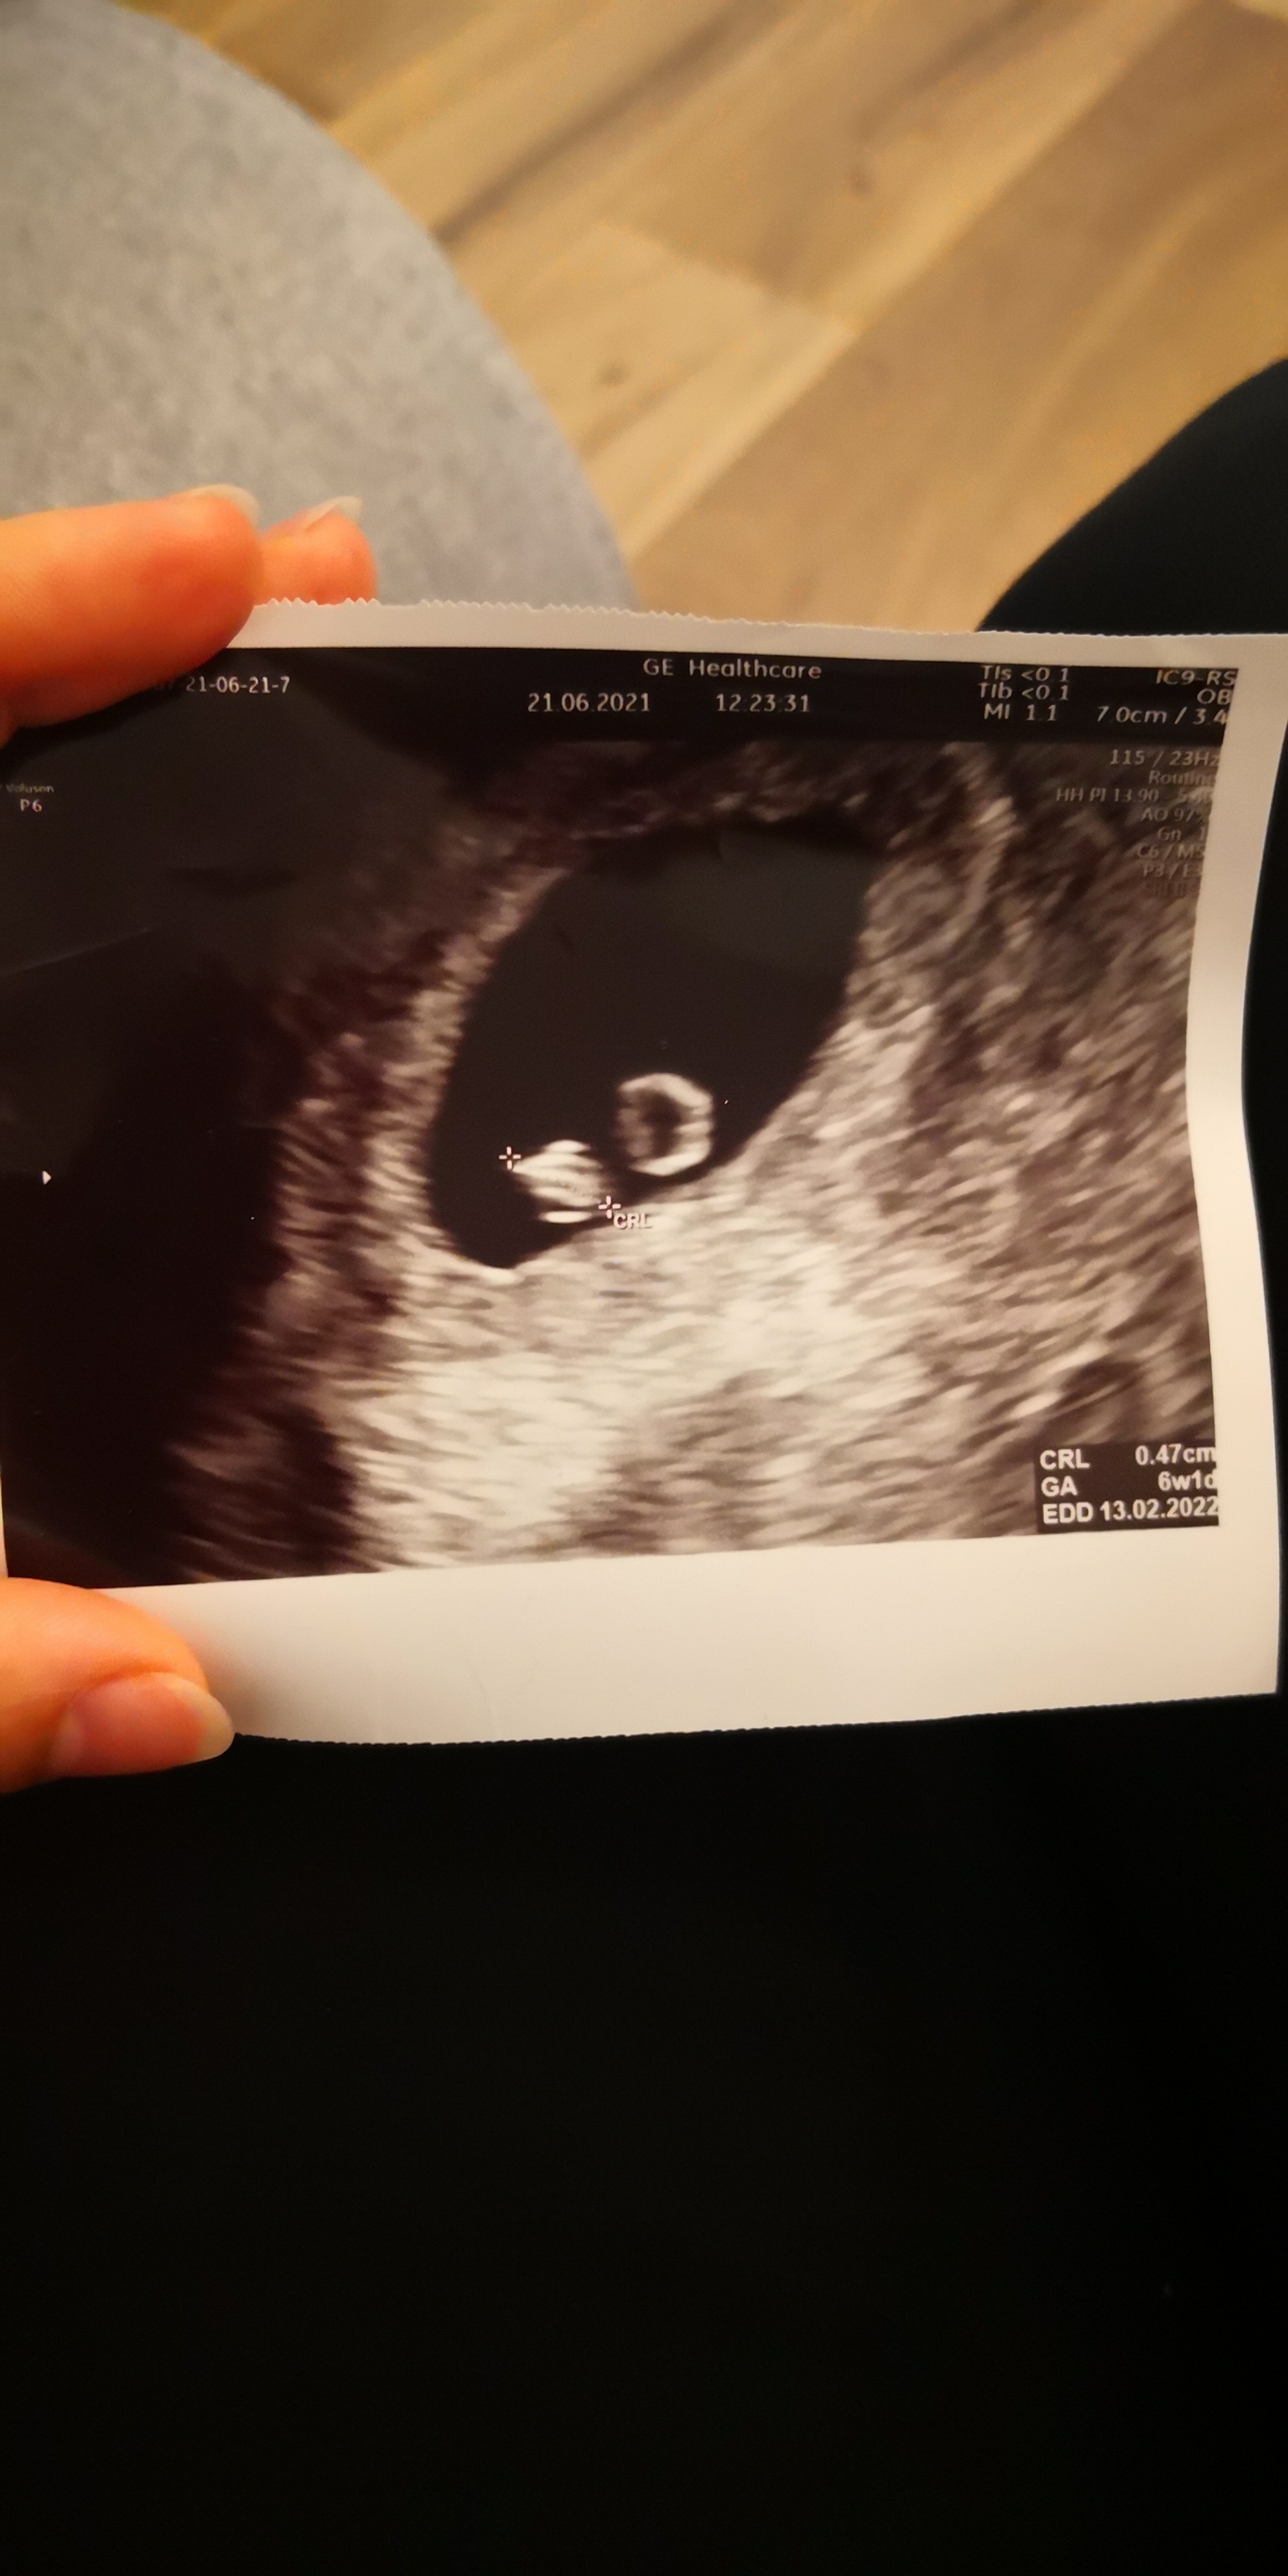

Czy to ciąża bliźniacza?

Hej, czy to ciąża bliźniacza?

Ginekolog nic mi nie powiedział, kazał przyjść za tydzień. Jeszcze tydzień nie minął a ja zaraz zwariuje. :) w jednym bombelku widoczne było serduszko, w drugim nie. Wg usg to 6 tydzień.